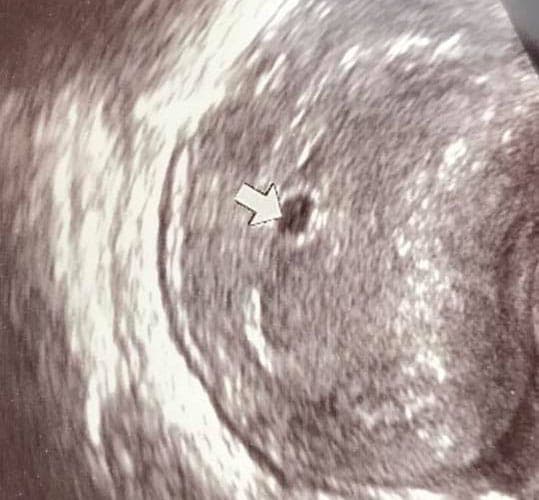

Was kann man auf einem Ultraschallbild erkennen?

Was genau man auf einem Ultraschallbild erkennen kann, hängt nicht nur von der Größe des Babys ab, sondern auch davon wie gut das Ultraschall-Gerät ist, mit dem die Aufnahme gemacht wurde. Auch auf den Ultraschallbildern hier kannst du sehen, dass die Qualität stark schwankt. In der Regel kann man gut den Kopf und RUmpf des Babys erkennen und auch die Gliedmaßen erkennt man selbst als Laie gut.

Wer sich jedoch erhofft Gesichtszüge zu erkennen, der wird oft enttäuscht. Zwar kann man beim 3D-Ultraschall schon eine Menge sehen, aber das umgebende Fruchtwasser sorgt in den allermeisten Fällen für starke Störungen.